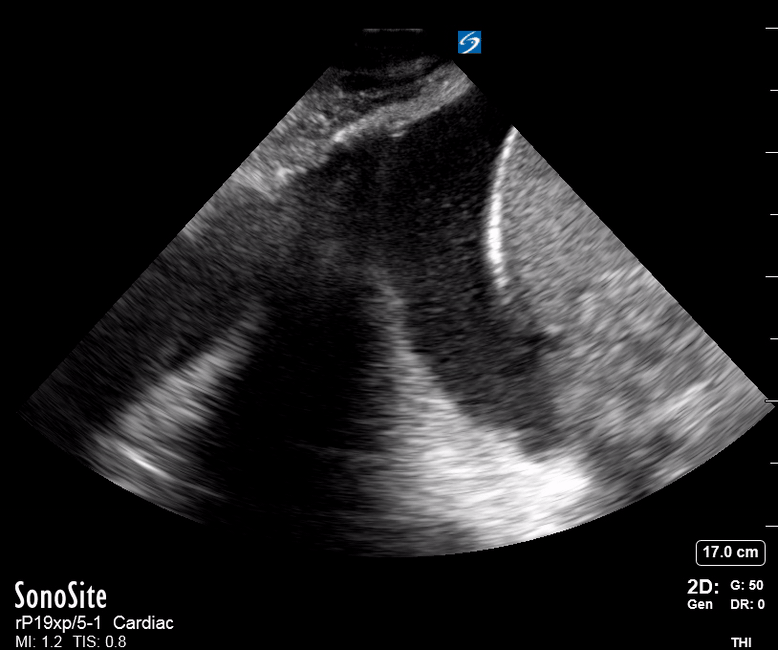

Effusion: is there a pericardial or pleural effusion?

Pericardial effusion is a continuum and can potentially evolve into haemodynamic collapse. Tamponade physiology is detectable earlier with ultrasound than with traditional physical examination, and it has been demonstrated that PoCUS improves mortality in penetrating cardiac trauma. Timely and accurate diagnosis is, therefore, vital.

THE VIEWS

The subxiphoid view is the most reliable for detecting pericardial effusion. Still, it is ideal to obtain different views not to miss a focal effusion as small amounts of fluid can lead to tamponade physiology. Tamponade does not link strictly to the size of the effusion, but correlates more with the speed of onset, causes, and haemodynamic effects.

PITFALLS & PLEURAL EFFUSIONS

A common error is to confuse a pericardial fat pad with effusion. Fatty tissue has a heterogeneous echotexture, moving in coordination with the myocardium, and it cannot be tracked around the heart, especially posteriorly and to the apex. Another pitfall is misinterpreting a pleural effusion as a pericardial effusion. However, they can be differentiated by their relationship to the descending aorta. Pericardial effusion may be seen between the aorta and the LV free wall, whereas pleural effusions are posterior to the descending aorta. Lastly, other causes, namely hypovolaemia and large pleural effusions, can cause RA and RV collapse.

CARDIAC TAMPONADE

Progressively rising pressure translates into evolving tamponade, and this accompanies a series of ultrasound findings:

Initially, the RA collapses during ventricular systole (closed AV valves).

Followed by RV collapse in ventricular diastole (open AV valves).

Ultimately leading to LV collapse.

In addition, the presence of a non-collapsible, plethoric IVC is one of the most sensitive signs of tamponade, and a finding easy to visualise. Conversely, a pericardial effusion in a haemodynamically stable patient with a collapsible IVC is unlikely to represent tamponade.

Chamber collapse can be assessed in M-mode, where the collapsing RV is seen as a notch that takes place right after the mitral valve opening and before its closure (during diastole).